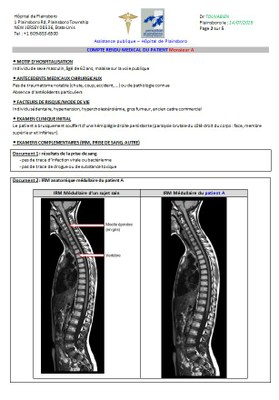

Activité pédagogique IRM médullaire + IRM cérébral et motricité

Figures et documents activité IRM médullaire + cérébral et motricité

Dossier medical 2b.JPG